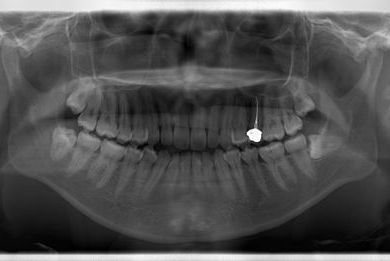

治療前

• 治療前